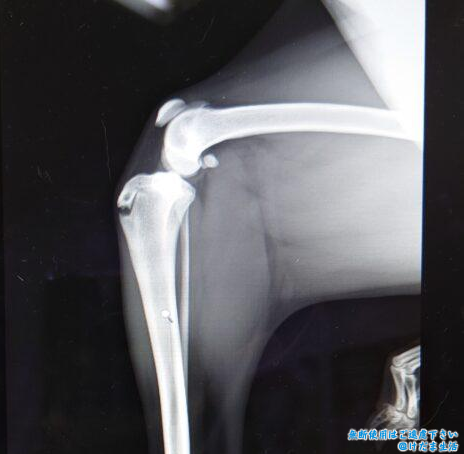

獣医さんはつるちゃんの抵抗や違和感のあるポイントを探し出してくれて、左前足の薬指と手首、右前足の人差し指、左ヒザに抵抗を示すのでポイントを絞ってレントゲン検査。

レントゲンの結果も関節液の増加などの炎症は見られず、前足は正常。

しかし1歳過ぎの時点で両膝の成長板が閉じてないことが判明。

2歳過ぎた頃から痛がることはなくなったので、骨の成長がゆっくりだったのは小型犬ではないことと避妊手術の時期も関係するのかなと思います。